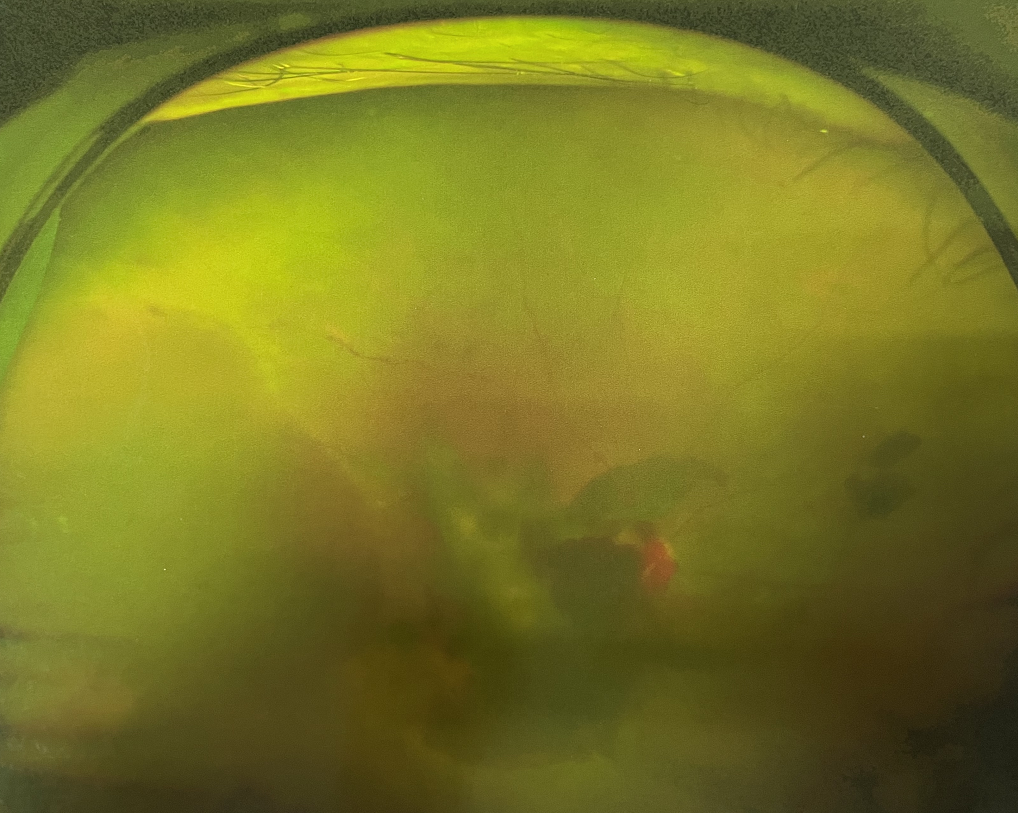

眼底病專(zhuān)科張小虎醫(yī)生檢查后,診斷王女士為“雙眼玻璃體積血、雙眼糖尿病視網(wǎng)膜病變V期”。(V期即5期,纖維增生期,出現(xiàn)纖維膜,可伴視網(wǎng)膜前出血或玻璃體出血。)

張小虎醫(yī)生為王女士進(jìn)行右眼玻璃體腔注藥術(shù),3天后進(jìn)行右眼23G玻璃體切割術(shù)后視力有所提升。

右眼術(shù)前